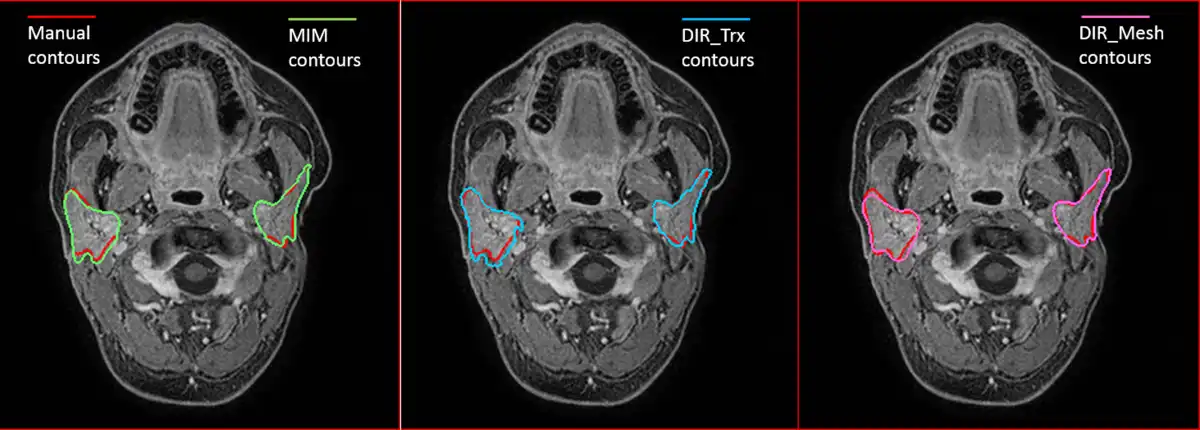

Qualitative results of contour propagation using MIM, DIR_Trx, and DIR_Mesh are presented in Figure 2, showing a good agreement between the manual reference contours and the propagated ones, without evident differences among the 3 methods. Quantitative results of contours evaluation are reported in Table 3. Average symmetric distance, MSD, and DSC indices calculated on both PGs for all patients and for all 3 considered DIR methods are plotted in Figure 3. DIR_Mesh presented the lowest average values of ASD and MSD and the highest average value of DSC over the population among the 3 methods, although nonsignificant (P values of the nonparametric Kruskal-Wallis test = 0.57, 0.40, and 0.27 for ASD, MSD, and DSC, respectively). The average propagation errors with respect to the reference contours are lower than the voxel diagonal (2 mm), and DSC is around 0.8, generally considered as the threshold for good agreement.

Figure 2

Examples of contour propagation using MIM (left), DIR_Trx (center), and DIR_Mesh (right) methods. Manual reference contours are also reported in red.